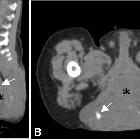

orbital heterotopic brain tissue

intraorbitales ektopes Hirngewebe